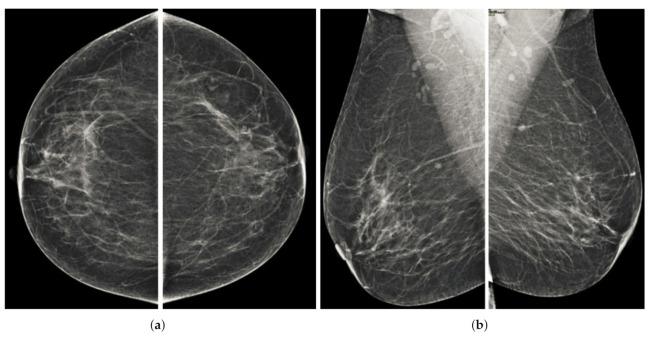

Breast cancer is widespread around the world and can be cured if diagnosed at an early stage. Digital mammograms are used as the most effective imaging modalities for the diagnosis of breast cancer. However, mammography images suffer from low contrast, background noise as well as contrast as non-coherency among the regions, and these factors makes breast cancer diagnosis challenging. These problems can be overcome by using a new image enhancement technique. The objective of this research work is to enhance mammography images to improve the overall process of segmentation and classification of breast cancer diagnosis. We proposed the image enhancement for mammogram images, as well as the ablation of the pectoral muscle. The image enhancement technique involves several steps. In the first step, we process the mammography images in three channels (red, green and blue), the second step is based on the uniformity of the background on morphological operations, and the third step is to obtain a well-contrasted image using principal component analysis (PCA). The fourth step is based on the removal of the pectoral muscle using a seed-based region growth technique, and the last step contains the coherence of the different regions of the image using a second order Gaussian Laplacian (LoG) and an oriented diffusion filter to obtain a much-improved contrast image. The proposed image enhancement technique is tested with our data collected from different hospitals in Qassim health cluster Qassim province Saudi Arabia, and it contains the five Breast Imaging and Reporting System (BI-RADS) categories and this database contained 11,194 images (the images contain carnio-caudal (CC) view and mediolateral oblique(MLO) view of mammography images), and we used approximately 700 images to validate our database. We have achieved improved performance in terms of peak signal-to-noise ratio, contrast, and effective measurement of enhancement (EME) as well as our proposed image enhancement technique outperforms existing image enhancement methods. This performance of our proposed method demonstrates the ability to improve the diagnostic performance of the computerized breast cancer detection method.